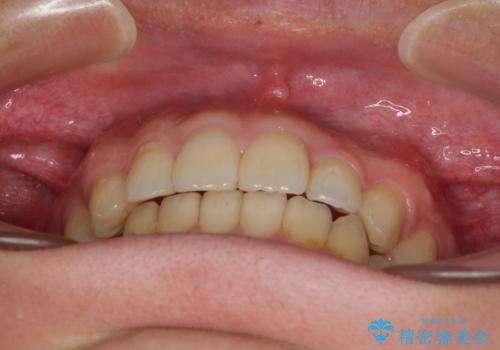

前歯のクロスバイトと抜歯が必要な奥歯の虫歯 インビザラインとインプラント治療

- 前歯のクロスバイトと、大学生のころから放置している虫歯を気にして来院された患者様です。

マウスピースでの矯正治療を希望されていましたが、前歯のクロスバイトは不十分な仕上がりや歯髄壊死などのリスクが高くなるため、術前にワイヤーで大まかに整えてからインビザラインにて矯正治療を行うこととしました。

奥歯の虫歯は抜歯が必要であったので、矯正治療前に抜歯をし、矯正治療と並行してインプラントによる補綴治療を行うこととしました。

当院の特徴は、矯正治療とインプラント補綴治療の担当医が同じ歯科医師であるため、両方の治療を並行して行うことができます。